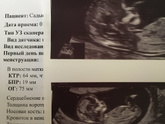

Сегодня был скрининг 12 недель 1 день, и у нас всё отлично) предложение что мальчик уж больно торчун чёткий ? размер от попы до темечка 6см 4мм, и вес 65 грамм) раскинул ноги и иногда махал ручками и ножками )

Сходили на узи

Всё прекрасно, срок соответствует, сердцебиение подтвердили, шов состоятельный)